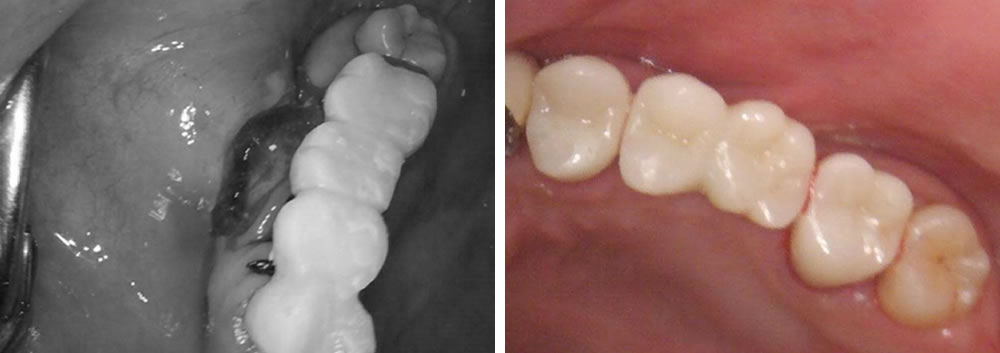

まずブリッジを除去し、残す事のできない歯を抜き、元々歯のない部位と歯を抜いた部位にインプラント治療を行いました。歯を抜き、即時でインプラントを入れる部位には埋入と同時に骨を作る処置(骨造成)を行い、特殊な縫合で傷口を閉鎖し、歯茎の形態も同時に調整していきました。

次に右下のブリッジの入っている部位もインプラントに変えていきたいとの希望により、ブリッジを除去し歯の無い部位にインプラントを埋入しました。

元々歯の無い部位に行う埋入は7ミリ程度の切開にて行いました。低侵襲で行う事により、痛み腫れを最小限に抑えて施術を行う事ができました。